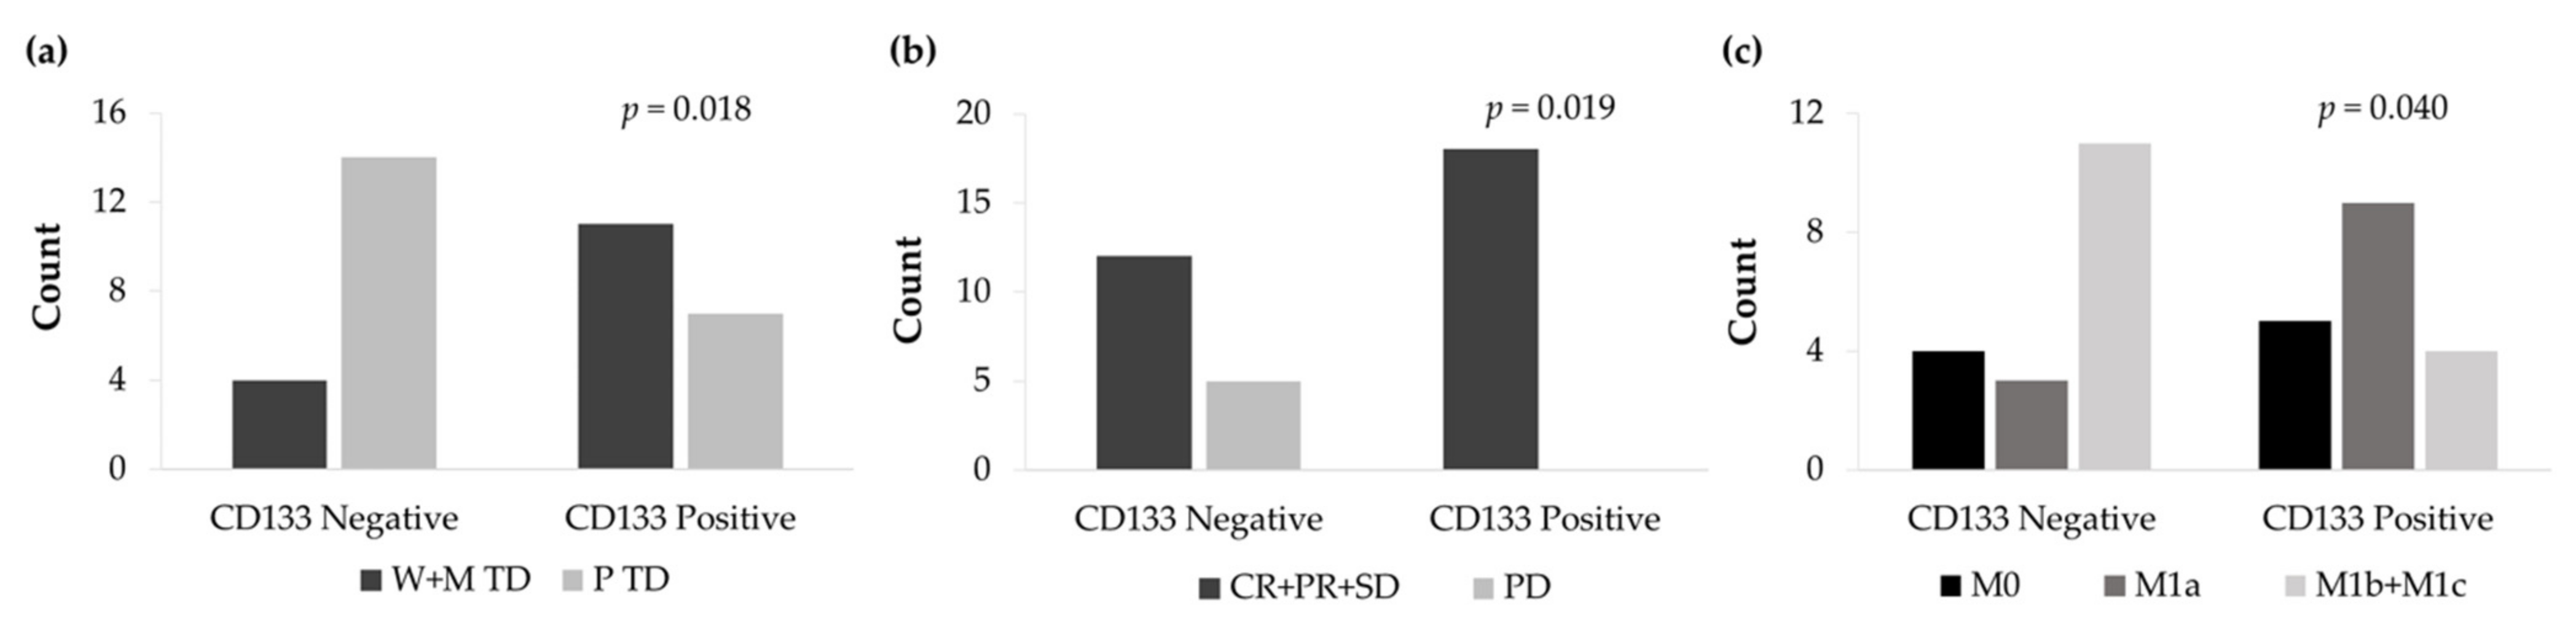

3.6. CD133 and Vimentin Expression in EGFRm NSCLC Patient-Derived Tumors

3.6.1. Patient and Tumor Characteristics

3.6.2. CD133 and Vimentin Tumor Expression in EGFRm NSCLC Patients